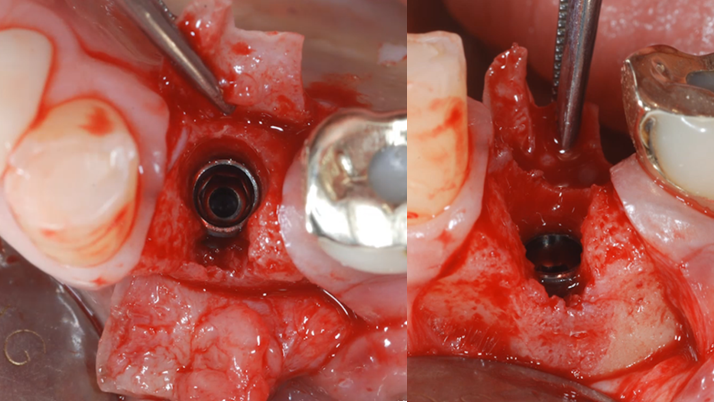

Clinical case: : R2GATE guided surgery & immediate implant placement

- Courtesy of Dr. Kwang Bum Park, Korea -

Keywords

Dr. Kwang Bum Park, immediate loading, digital guided surgery, digital ONE-DAY implant, maxillary anterior, #21, guided surgery, immediate loading, AnyRidge, R2GATE, Mega ISQ, MEG Torq, R2GATE Full Surgical Kit

Products:

implant system, R2GATE Guide, R2GATE full surgical kit, Mega ISQ